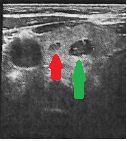

Cervical ultrasound. Green arrow: Papillary carcinoma. Red arrow: Medullary carcinoma (Courtesy Dr. V. Penopoulos)